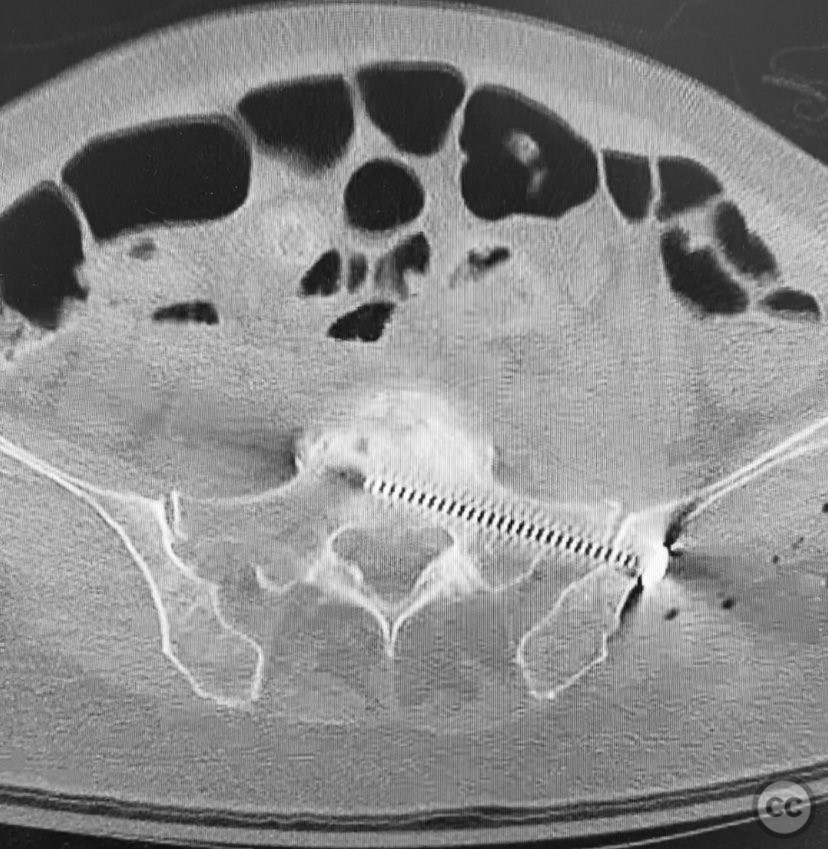

Planning remarks:  The preoperative plan involved closed reduction of the pelvic ring under fluoroscopic guidance, followed by percutaneous screw fixation of the left posterior iliac/sacral region and the ipsilateral pubic ramus. Detailed preoperative CT imaging was used to plan safe osseous corridors for screw placement, correlating with intraoperative fluoroscopic landmarks.

Anatomical surgical approach:  Percutaneous technique was employed. Small stab incisions were made over the lateral aspect of the pelvis. Under continuous fluoroscopic guidance, guidewires were advanced through the ilium into the sacrum (iliosacral region) and through the superior pubic ramus. Cannulated screws were then inserted over the guidewires, ensuring extra-articular and intraosseous positioning within the safe bone corridors as determined by preoperative CT analysis.